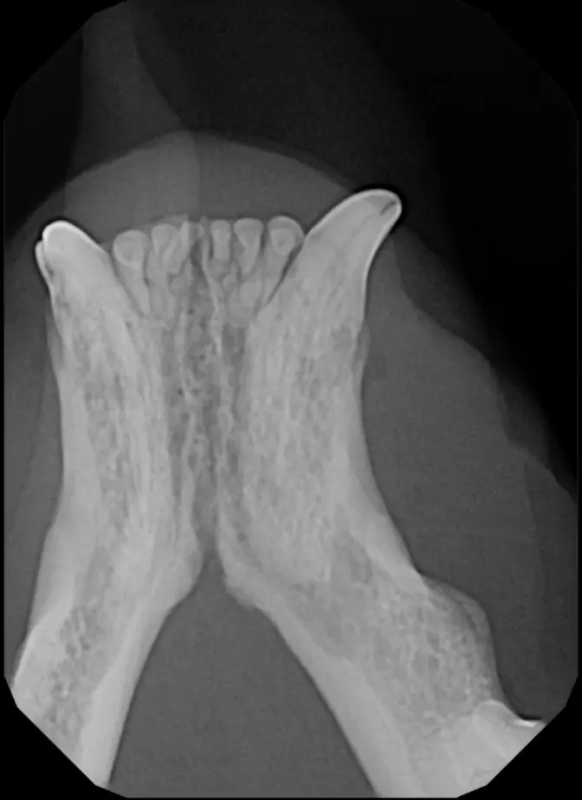

The Center now provides advanced imaging via cone beam CT. Cone beam CT is excellent for visualization of bony structures of the skull, nasal cavity, teeth, and ears. Cone beam CT is especially helpful for diagnosing dental disease and evaluation of jaw fractures. It can also be useful for evaluating the sinuses and tympanic bulla. Cone beam CT can be used in conjunction with nasal biopsy and culture to evaluate nasal discharge whether chronic or acute.

Periodontal disease is extremely common in dogs and cats. Over 80% of dogs and cats over two years of age have some degree of periodontal disease. Periodontal disease is best prevented by yearly professional dental cleanings starting at two years of age and at home brushing at least three times weekly. Brushing should begin at a very early age to allow your new pet to get used to regular brushing. In severe cases of infection or periodontal disease, the teeth may need to be surgically extracted. Extractions should always involve x-rays of the tooth first, as many teeth have multiple roots or may be diseased below where the eye can see. Extracting larger teeth in animals requires oral surgery, equivalent to removing wisdom teeth in people. It is vital that all of the tooth and roots be removed for the periodontal infection to resolve. In cases of important teeth with mild to moderate periodontal disease, multiple periodontal treatments can be offered to help save these teeth.

Pets can be involved in trauma that can cause fractures to their head, teeth, and jaw bones. Correctly repairing these fractures is extremely important for your pet to have normal function of their mouth. If a jaw fracture is allowed to heal in an abnormal position, your pet may have great difficulty chewing and can be in significant pain. Many fractures can be successfully treated with minimally invasive oral procedures, but more complicated cases may require bone plating techniques. The Center offers cone beam CT imaging which provides extremely detailed images of the bones of the head and skull. Advanced imaging with CBCT facilitates selection of the best surgical technique to get your pet back to eating and comfort as soon as possible.